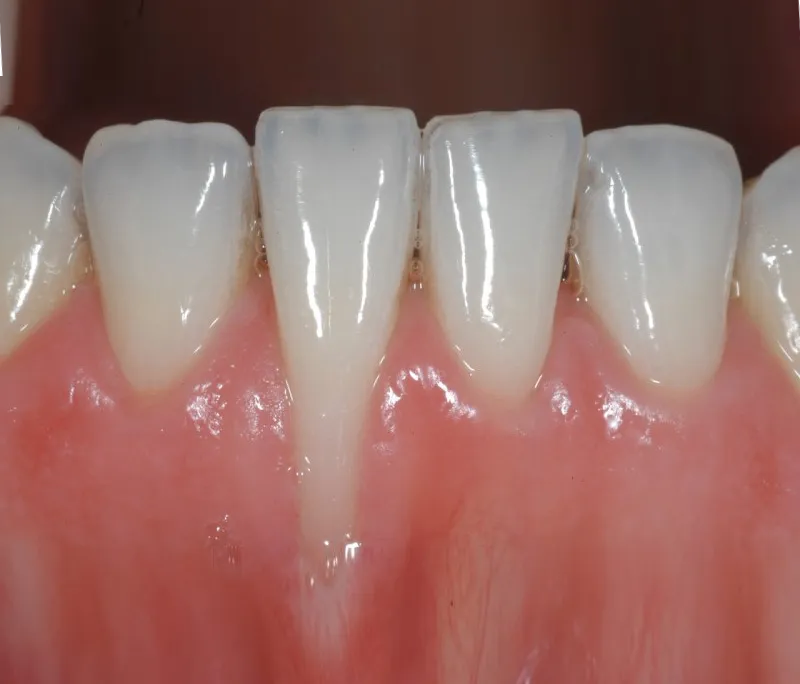

Vấn đề tụt lợi không chỉ gây ê buốt, khó chịu mà còn ảnh hưởng đến thẩm mỹ nụ cười. Bạn đang có ý định ...

>> Xem ngayVấn đề tụt lợi không chỉ gây ê buốt, khó chịu mà còn ảnh hưởng đến thẩm mỹ nụ cười. Bạn đang có ý định ...